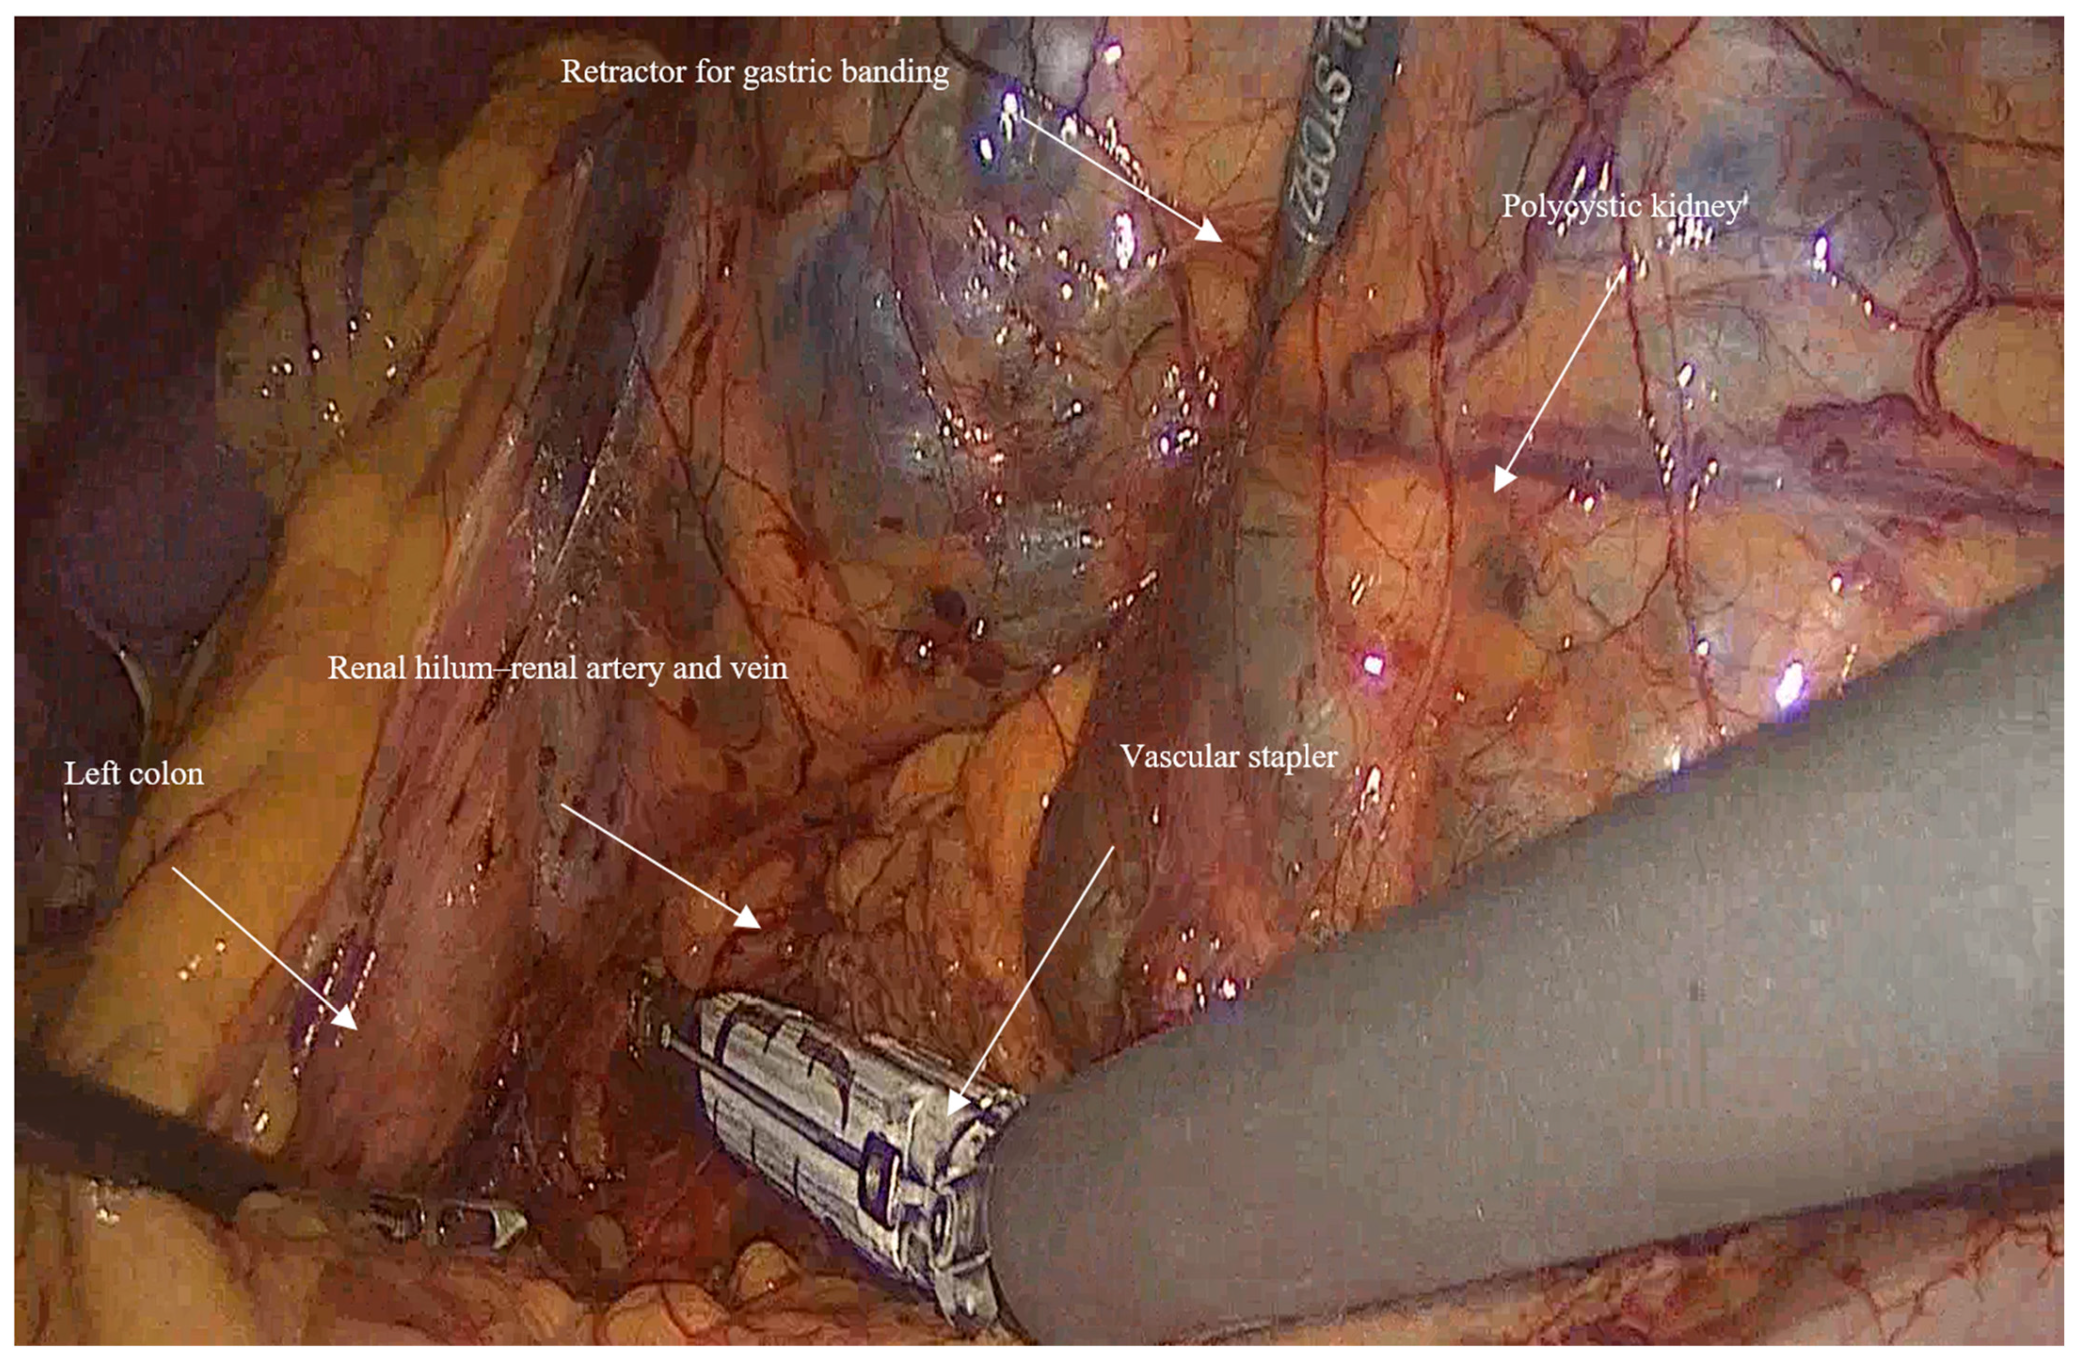

- Mobilization: Initially, the left colon was mobilized laterally, and Gerota’s fascia was identified. Careful dissection was performed to reveal the kidney Figure 1.

- Vascular control and ligation: The renal artery and vein were clamped together close to the hilum of the kidney using a vascular stapler (SigniaTM with Tri-StapleTM reinforced reloads, Medtronic, Minneapolis, MN, USA). Following that, a dissection of the rest of the inferior border of the kidney is completed, and then the ureter is ligated using Hem-o-lock™ clips (Weck, Research Triangle, NC, USA; Figure 2).

- In huge kidney with previous infections where controlled aspiration may be hazardous, a sufficient retraction with a retractor for Gastric Banding (Karl Storz 30,623 GB), which has a 0-to-90-degree angle of its tip and can provide an efficient retraction and elevation of the huge kidney from the psoas muscle and assist in gaining access to the hilum of the kidney (Figure 3).